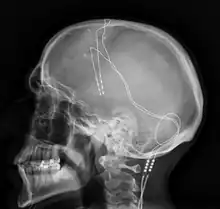

DBS-probes shown in X-ray of the skull (white areas around maxilla and mandible represent metal dentures and are unrelated to DBS devices)

Components and placement

The DBS system consists of three components: the implanted pulse generator (IPG), the lead, and an extension. The IPG is a battery-powered neurostimulator encased in a titanium housing, which sends electrical pulses to the brain that interfere with neural activity at the target site. The lead is a coiled wire insulated in polyurethane with four platinum-iridium electrodes and is placed in one or two different nuclei of the brain. The lead is connected to the IPG by an extension, an insulated wire that runs below the skin, from the head, down the side of the neck, behind the ear, to the IPG, which is placed subcutaneously below the clavicle, or in some cases, the abdomen.[8] The IPG can be calibrated by a neurologist, nurse, or trained technician to optimize symptom suppression and control side effects.[35]

DBS leads are placed in the brain according to the type of symptoms to be addressed. For non-Parkinsonian essential tremor, the lead is placed in either the ventrointermediate nucleus of the thalamus or the zona incerta;[36] for dystonia and symptoms associated with PD (rigidity, bradykinesia/akinesia, and tremor), the lead may be placed in either the globus pallidus internus or the subthalamic nucleus; for OCD and depression to the nucleus accumbens; for incessant pain to the posterior thalamic region or periaqueductal gray; and for epilepsy treatment to the anterior thalamic nucleus.

All three components are surgically implanted inside the body. Lead implantation may take place under local anesthesia or under general anesthesia ("asleep DBS"), such as for dystonia. A hole about 14 mm in diameter is drilled in the skull and the probe electrode is inserted stereotactically, using either frame-based or frameless stereotaxis.[37] During the awake procedure with local anesthesia, feedback from the person is used to determine the optimal placement of the permanent electrode. During the asleep procedure, intraoperative MRI guidance is used for direct visualization of brain tissue and device.[38] The installation of the IPG and extension leads occurs under general anesthesia.[39] The right side of the brain is stimulated to address symptoms on the left side of the body and vice versa.